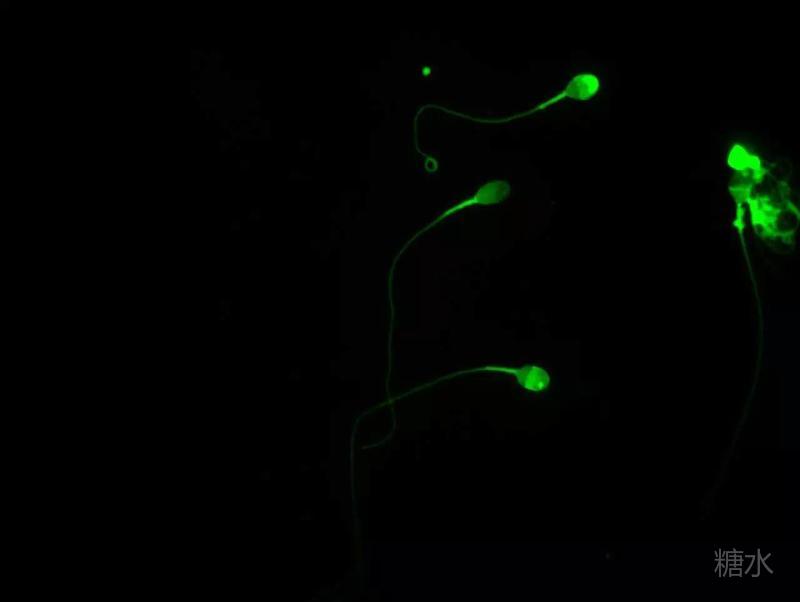

六 、低渗肿胀试验(简称:HOS):检测精子存活率的另一种方法,只有细胞膜完整的精子(活精子)能够在低渗溶液中膨胀,故可根据肿胀的精子的百分率得出精子存活率。检测精子活率,对于弱精子症、不动精子症等病例有重要意义。